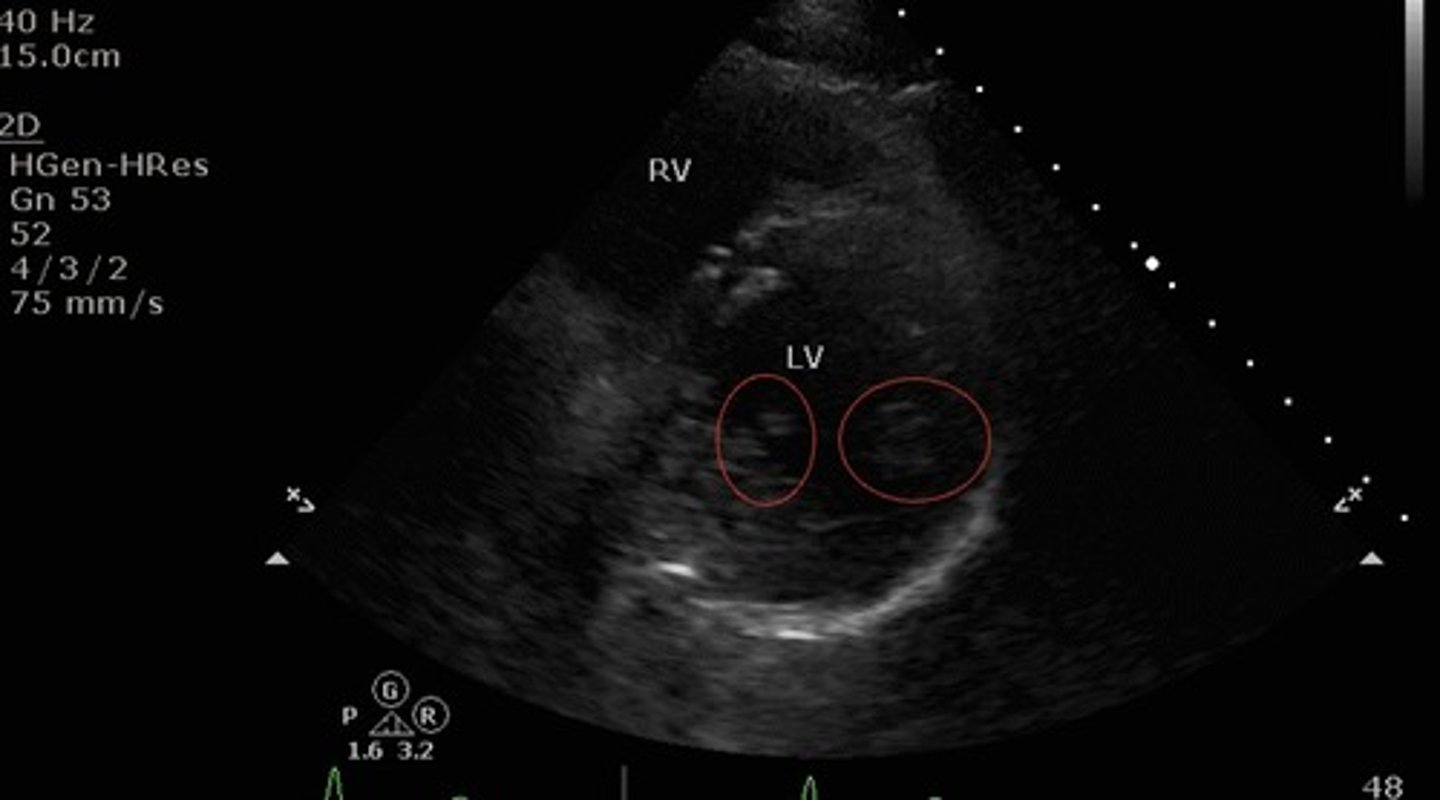

Parasternal short axis mid-ventricle

What view of the heart is this?

Papillary muscles

What structures are indicated by the red circles?

what structures are seen with parasternal short axis mid-ventricular view?